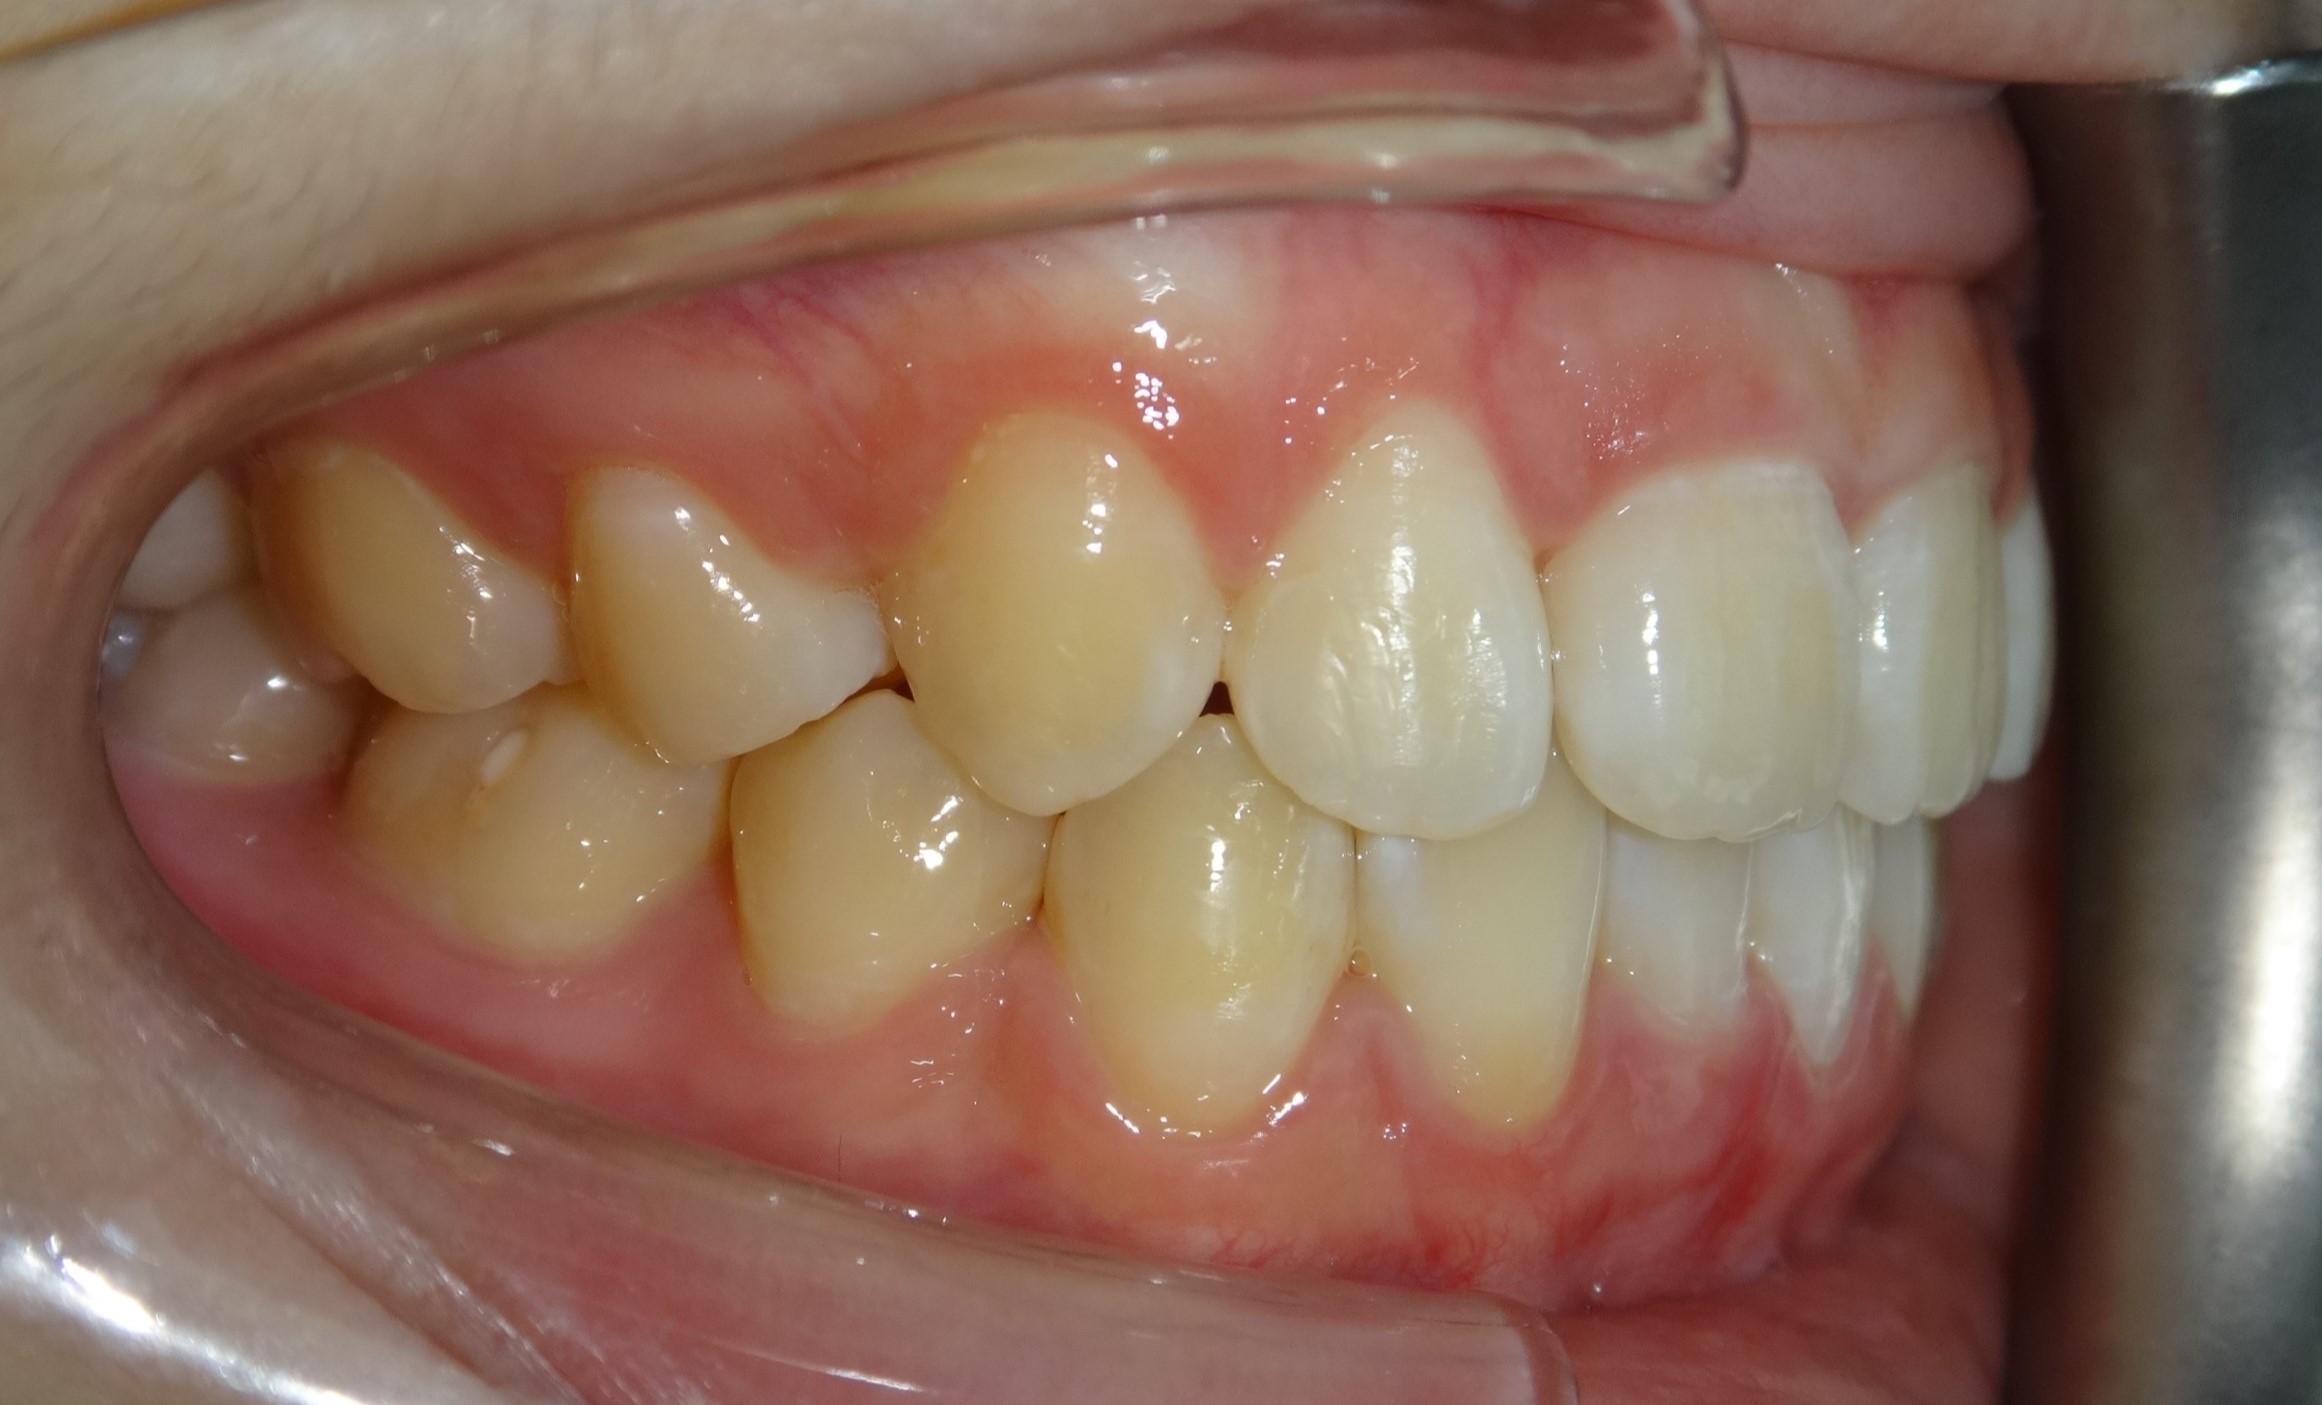

拔牙案例 首頁 案例分享 齒顎矯正 拔牙案例 - 拔牙案例 - 年紀:15歲 矯正方式:隱適美隱形矯正 時間:30個月 主訴:暴牙、笑起來不好看、咬合不正 矯正前 矯正後 矯正前 矯正後 矯正前 矯正後 聲明:本所療程皆由專業醫生評估後,依照個人口腔狀況進行治療。因每位患者個別狀況不同,術後狀況也不盡相同,需親來本所由醫生評估。